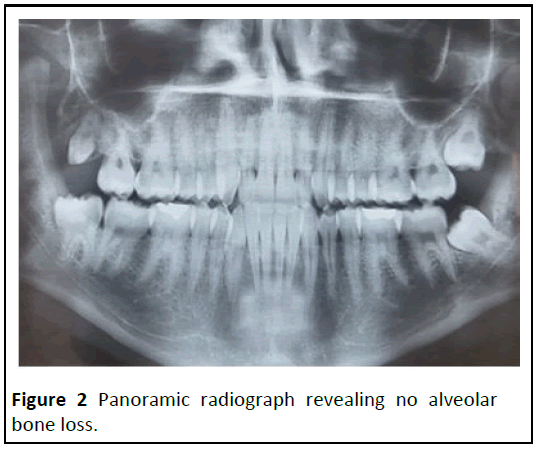

Clinical examination indicated a pseudo membrane formation along the gingival edges, as well as headless ulcerated papillae, particularly on the upper anterior teeth and lower central incisors (Figure 1). In rare cases, the papilla did not completely fill the interproximal area. On the teeth surfaces, there was a generalised and extensive deposit of dental plaque. X-rays revealed periodontal ligament expansion in the lower central incisors but no alveolar bone loss (Figures 2 and 3). During the physical examination, no systemic condition that could predispose the patient to NUG was discovered. However, the patient indicated that he had been under considerable stress and psychological pressure at school as a result of a period of academic probation. Based on the clinical data obtained at the examination, NUG was diagnosed [3].

Figure 2: Panoramic radiograph revealing no alveolar bone loss.